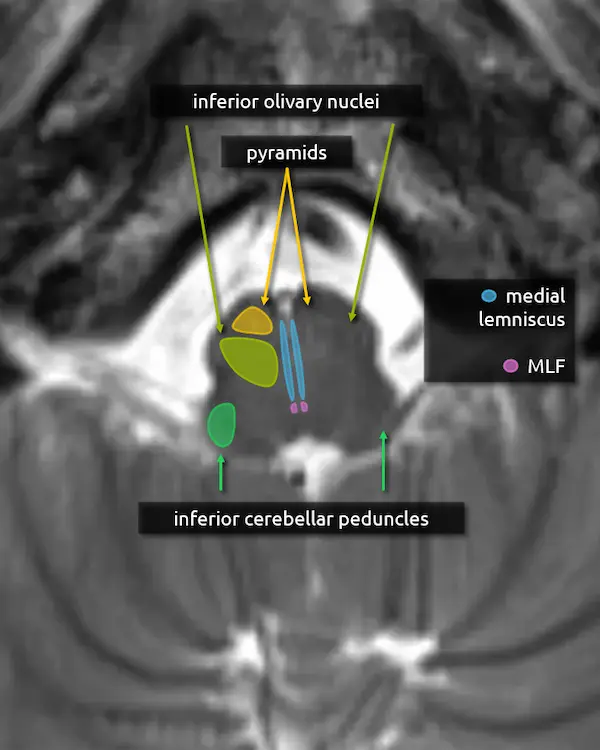

1. Pyramids:

The medullary pyramids contain the corticospinal tract and corticobulbar tract, which are sometimes collectively called the pyramidal tracts. They are named due to the shape they form on the ventral surface of the medulla, which usually becomes more pyramid-like inferiorly.

2. Inferior cerebellar peduncles:

The inferior cerebellar peduncles are the smallest of the three, making them difficult to recognize in the axial plane. They contain mostly afferent and few efferent fibers.

Hyperintensity of the inferior cerebellar peduncle has recently been proposed as a specific feature of multiple system atrophy cerebellar type (MSA-C), helping differentiate it from spinocerebellar ataxia (inferior cerebellar peduncle sign).

1. Pyramids

2. Inferior cerebellar peduncles

3. Medial lemniscus

4. Medial longitudinal fasciculus (MLF)

5. Inferior olivary nucleus

The inferior olivary nucleus is located in the upper medulla just posterior to the pyramids. It is involved in motor coordination and is a main component of the dentatorubro-olivary pathway (aka the triangle of Guillain and Mollaret), discussed below. A lesion that damages the predominantly inhibitory interneurons in the tracts connecting the corners of the triangle may result in disinhibition of the inferior olivary nucleus, characteristically but rarely manifesting as palatal myoclonus. Over time, the inferior olivary nucleus may swell, become T2 hyperintense, and eventually atrophy, a process called hypertrophic olivary degeneration.